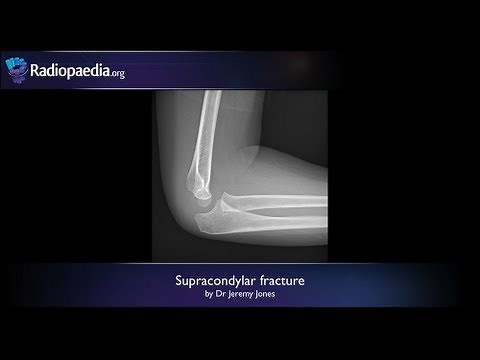

Condyle Fracture Surgery - Supracondylar

Fracture - Femoral Neck Fracture